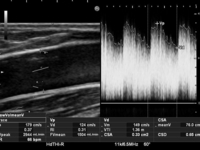

・上腕動脈血流量・RI

上腕動脈血流量・RIの測定については、基本的には上腕中間部と肘部の2ヵ所の上腕動脈で測定し、血流量に関しては、過大評価とならないよう、mean traceにより算出されるFv mean(平均流速における特定範囲の平均値)を参考にしています。

※上腕動脈血流:300~350ml/min以上、RI:0.6~0.7以下をカットオフ値とし、透析中の脱血の状態等も考慮し、必要に応じ血管外科等の受診を検討しています。